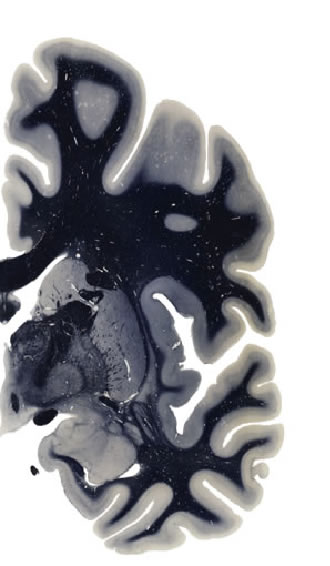

Hi-Resolution Sections · Cells (Nissl Staining) · Virtual Microscopy

Frontal sections (Nissl) from the Atlas Brain:

Slice ID:

r3-1171

Plate NR:

ca 26-27

Position:

6,1 mm